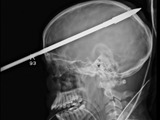

Le atraviesan el cerebro con un arpón

La historia de la supervivencia de López comenzó el 7 de junio. El joven de 16 años estaba nadando en un lago cerca de su casa. La policía dice que su amigo estaba cargando un arpón para pescar cuando disparó accidentalmente el gatillo.

Un par de semanas después los médicos dicen que es probable que López se recupere completamente. Por suerte, la lanza no dañó los centros del habla en su cerebro. "Sus palabras son en realidad sorprendentemente fáciles de entender", dijo el Dr. Ross Bullock. "Él dice que no tiene dolor y está preocupado por el hecho de que no puede utilizar su lado izquierdo correctamente".